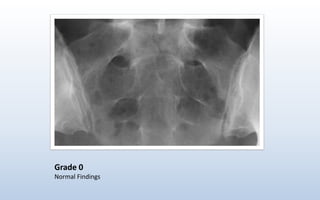

Grade 0

Normal Findings

Grading of Sacroilitis- New York Criteria Grade 0 : Normal Grade I : Some blurring of the joint margins - suspicious Grade II : Minimal sclerosis with some erosion Grade III : Definite sclerosis on both sides of joint Severe erosions with widening of joint space with or without ankylosis Grade IV : Complete Ankylosis